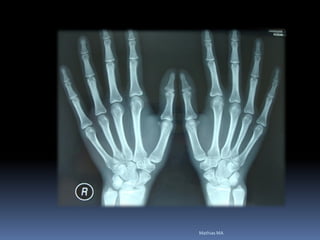

Exames hematológicos

Hemograma completo

• Coagulograma completo

•Glicemia em jejum

•Ca, P, fosfatase alcalina, creatinina, uréia

•Sorológicos ( Hepatite e AIDS)